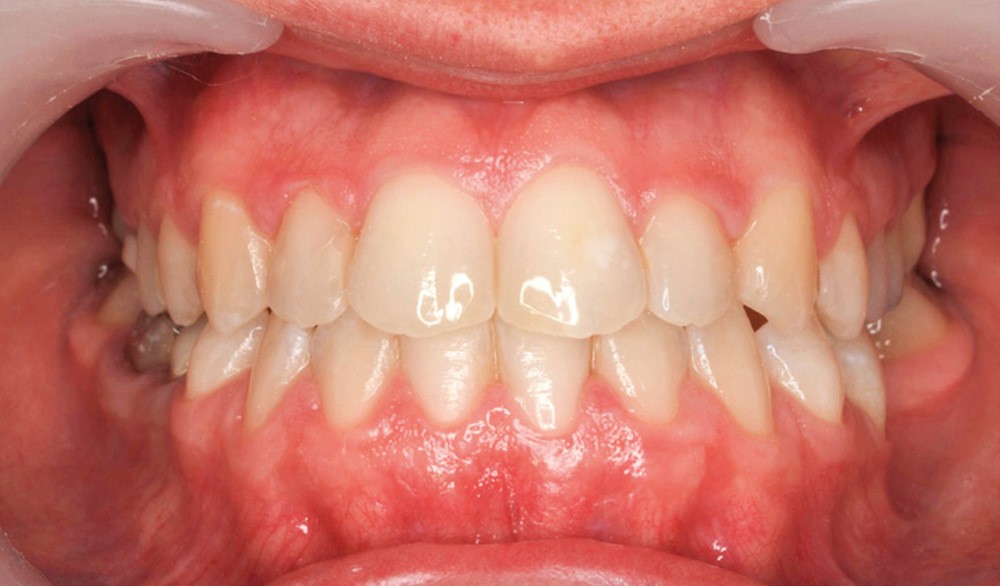

- Septième rendez-vous : les appareils sont déposés. Une empreinte numérique est prise pour réaliser trois aligneurs afin de parfaire le résultat occlusal et esthétique (fig. 3a-h).

L’outil 3D nous permet de contrôler et maîtriser la conception/fabrication des appareils linguaux et des aligneurs, combinant et optimisant ainsi avantageusement les qualités des deux appareils.

Finalement, les aligneurs permettent les ajustements occlusaux fins et précis de finition.